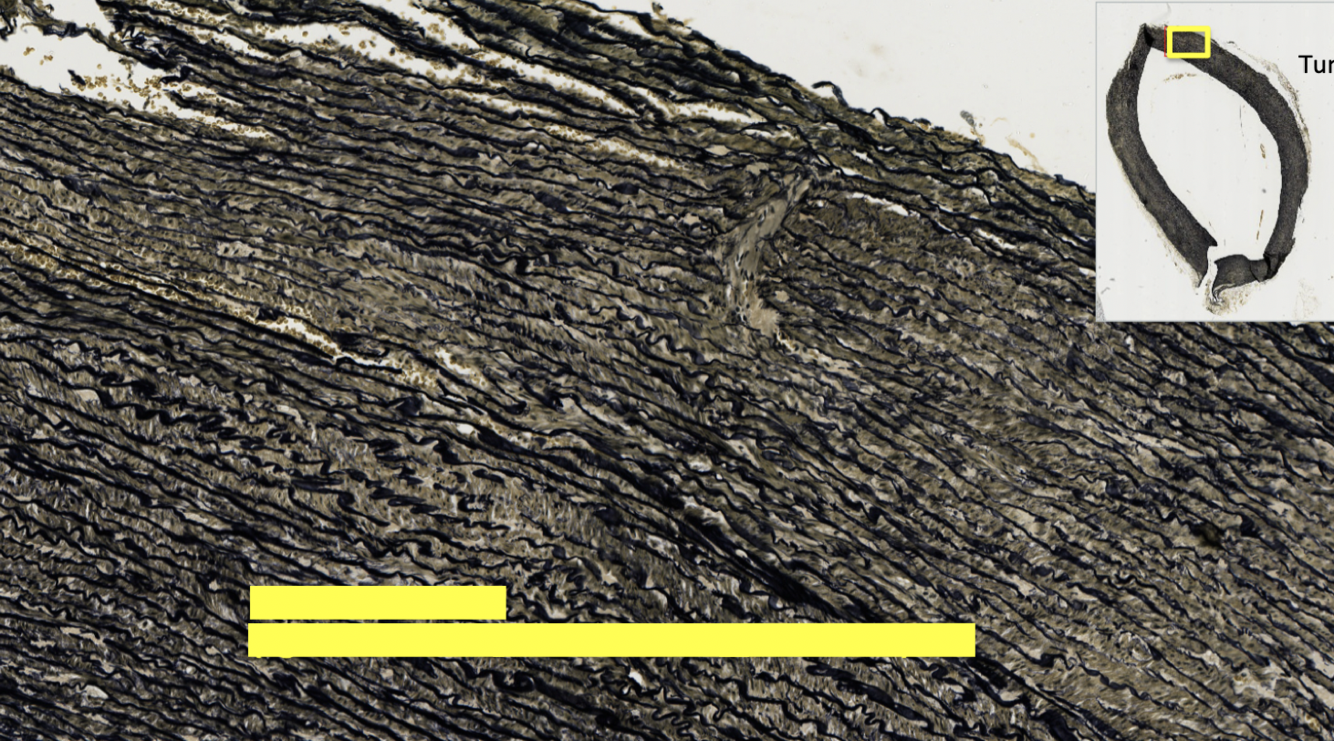

tunica intima composed of

tunica media composed of

shape of

artery

vein

rounder

flatter

wall of

thicker

thinner

tunica media of

more smooth muscle

less smooth muscle

lumen of

smaller

wider